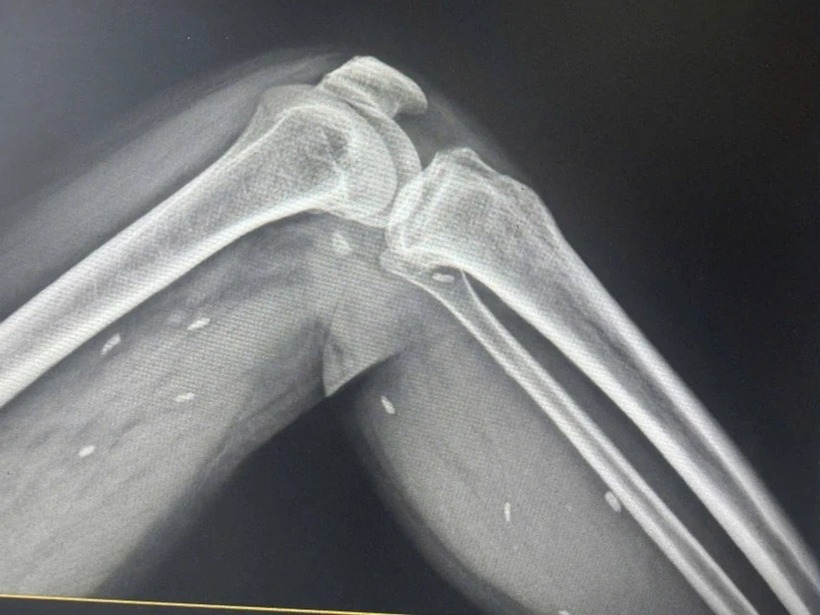

Nhiều kén sán kích thước như hạt gạo nằm rải rác ở các mô vùng xương đùi và cẳng chân bệnh nhân. Ảnh: PLO.

Qua kết quả chụp X- quang, BS Đỗ Hồng Thanh, Phó Giám đốc Trung tâm Y tế khu vực Thạch Hãn, cho biết phát hiện nhiều kén sán kích thước như hạt gạo nằm rải rác ở các mô vùng xương đùi và cẳng chân bệnh nhân.